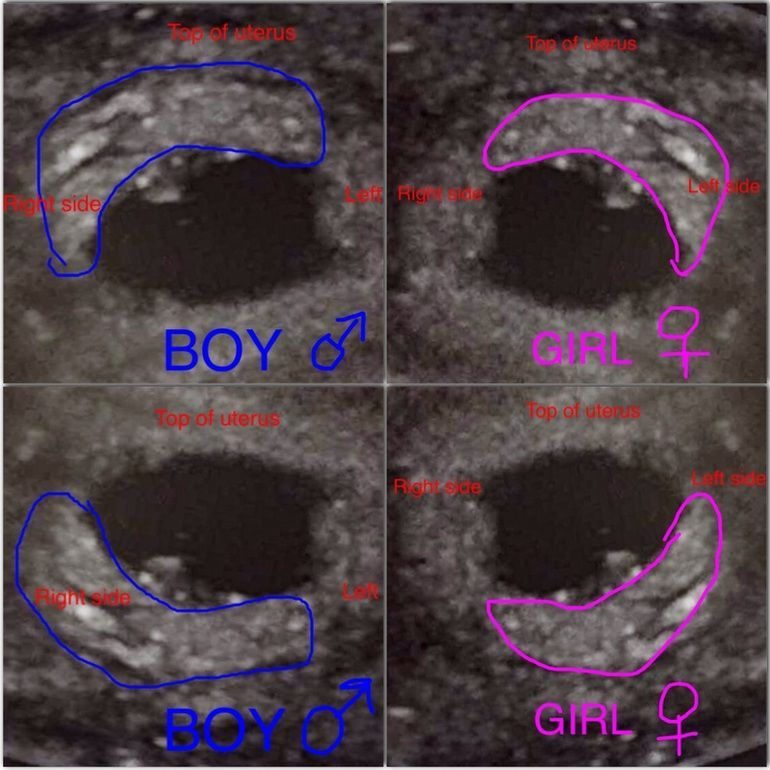

Пол ребёнка по расположению

Бред)) морула цепляется где эндометрий лучше, а не мальчики налево, девочки направо